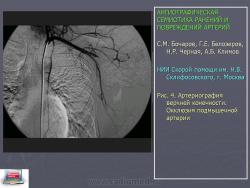

При закрытых повреждениях вследствие особенностей механизма травмы (ушиб, сдавление, размозжение или перерастяжение) наблюдаются следующие изменения сосудов: контузия стенки с ее разрывом, образование внутрисосудистой гематомы, отслойка интимы. Субинтимальная гематома может продолжить отслоение интимы. Продолжающееся отслоение интимы приводит к тому, что ее фрагменты флотируют в просвете сосуда, усугубляя отслоение и увеличивая препятствие кровотоку с каждым пульсовым толчком. Процесс заканчивается тромбозом (окклюзия) сегмента артерии (рис. 4). Это было одним из самых частых проявлений травматического повреждения артерий и встретилось в 28,8% наблюдений.

Рис. 4. Артериография верхней конечности. Окклюзия подмышечной артерии